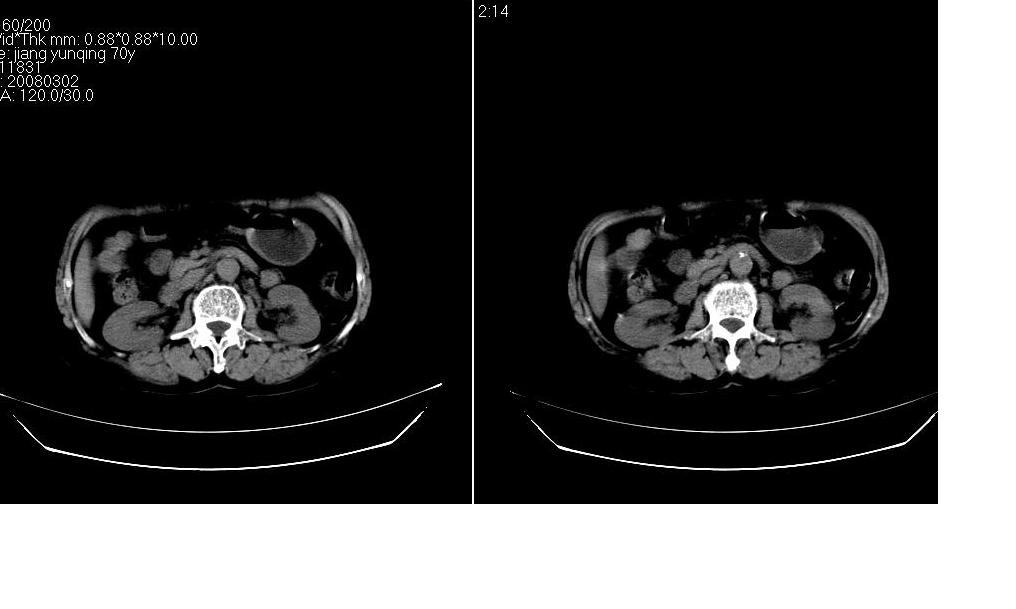

标题: CT12001:上腹部CT平扫

女73岁,病史不详,腹主动脉增宽.

腹主动脉夹层?

考虑:腹主动脉瘤。建议增强。

腹主动脉瘤是腹主动脉壁的扩张膨出。腹主动脉瘤发生后可逐渐增大,最后破裂出血,导致病人死亡。

腹主动脉瘤主要发生于60岁以上的老年人,常伴有高血压病和心脏疾病,但年轻人也偶尔可见。男性多于女性。腹主动脉瘤的发生主要与动脉硬化有关,其它少见原因是主动脉先天发育不良、梅毒、创伤、感染、大动脉炎、marfan综合征等。

考虑:腹主动脉瘤。建议增强排除夹层的可能。